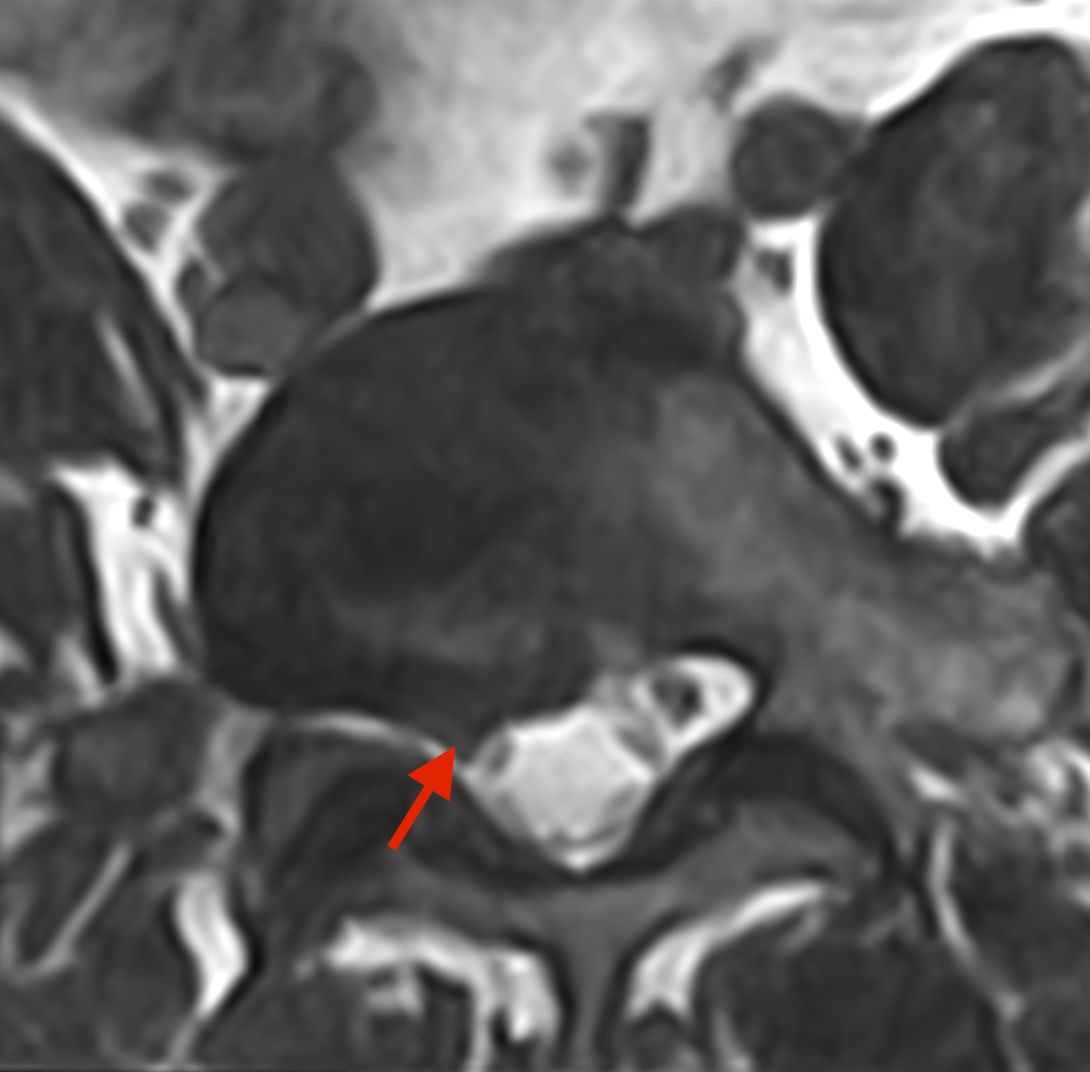

• ernia del disco cervicale, toracica e lombare;

• stenosi del canale vertebrale cervicale e lombare;